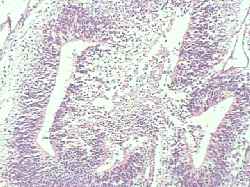

Imagen 4: Epitelio bronquial